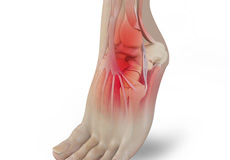

Septic Arthritis

Septic arthritis also called as infectious arthritis, is characterized by joint inflammation due to a bacterial or fungal infection that usually affects the large joints of the body such as knee or hip.